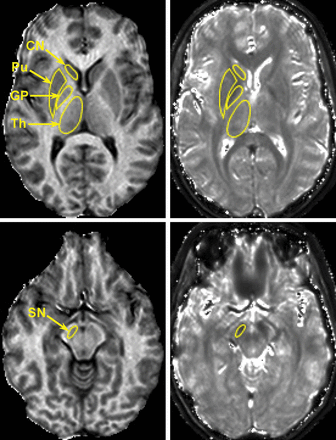

Representative cross-sections of 3D MPF (left) and T2* (right) maps obtained from a healthy female control subject (37 years of age) with superimposed ROIs corresponding to the head of caudate nucleus, globus pallidus, putamen (Pu), substantia nigra, and thalamus (Th). MPF and T2* maps are presented with gray-scale windows corresponding to the MPF range of 0%–20% and the T2* range of 0–100 ms.

Representative cross-sections of 3D MPF (left) and T2* (right) maps obtained from a female patient with SPMS (62 years of age; EDSS score, 5.5) with superimposed ROIs corresponding to the head of caudate nucleus, globus pallidus, putamen (Pu), substantia nigra, and thalamus (Th). MPF and T2* maps are presented with gray-scale windows corresponding to the MPF range of 0%–20% and the T2* range of 0–100 ms.

MPF maps enabled clear anatomic definition of subcortical GM structures based on their hypointensity relative to surrounding WM in all cases (Figs 1 and 2). The appearance of these structures on T2* maps was frequently obscured by the blooming effect, especially in the cases with excessive iron deposition (Fig 2). Manual MPF measurements were highly consistent between observers, with a coefficient of variation of <2.5% and an intraclass correlation coefficient of >0.9 (Table 1). T2* measurements demonstrated higher variability with a coefficient of variation in the range of 1.8%–10.3%, but they still had excellent overall agreement (intraclass correlation coefficient ≥ 0.8, Table 1).